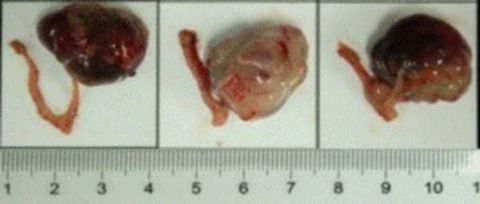

部分HJC黄金城平台PDX原位模型展示